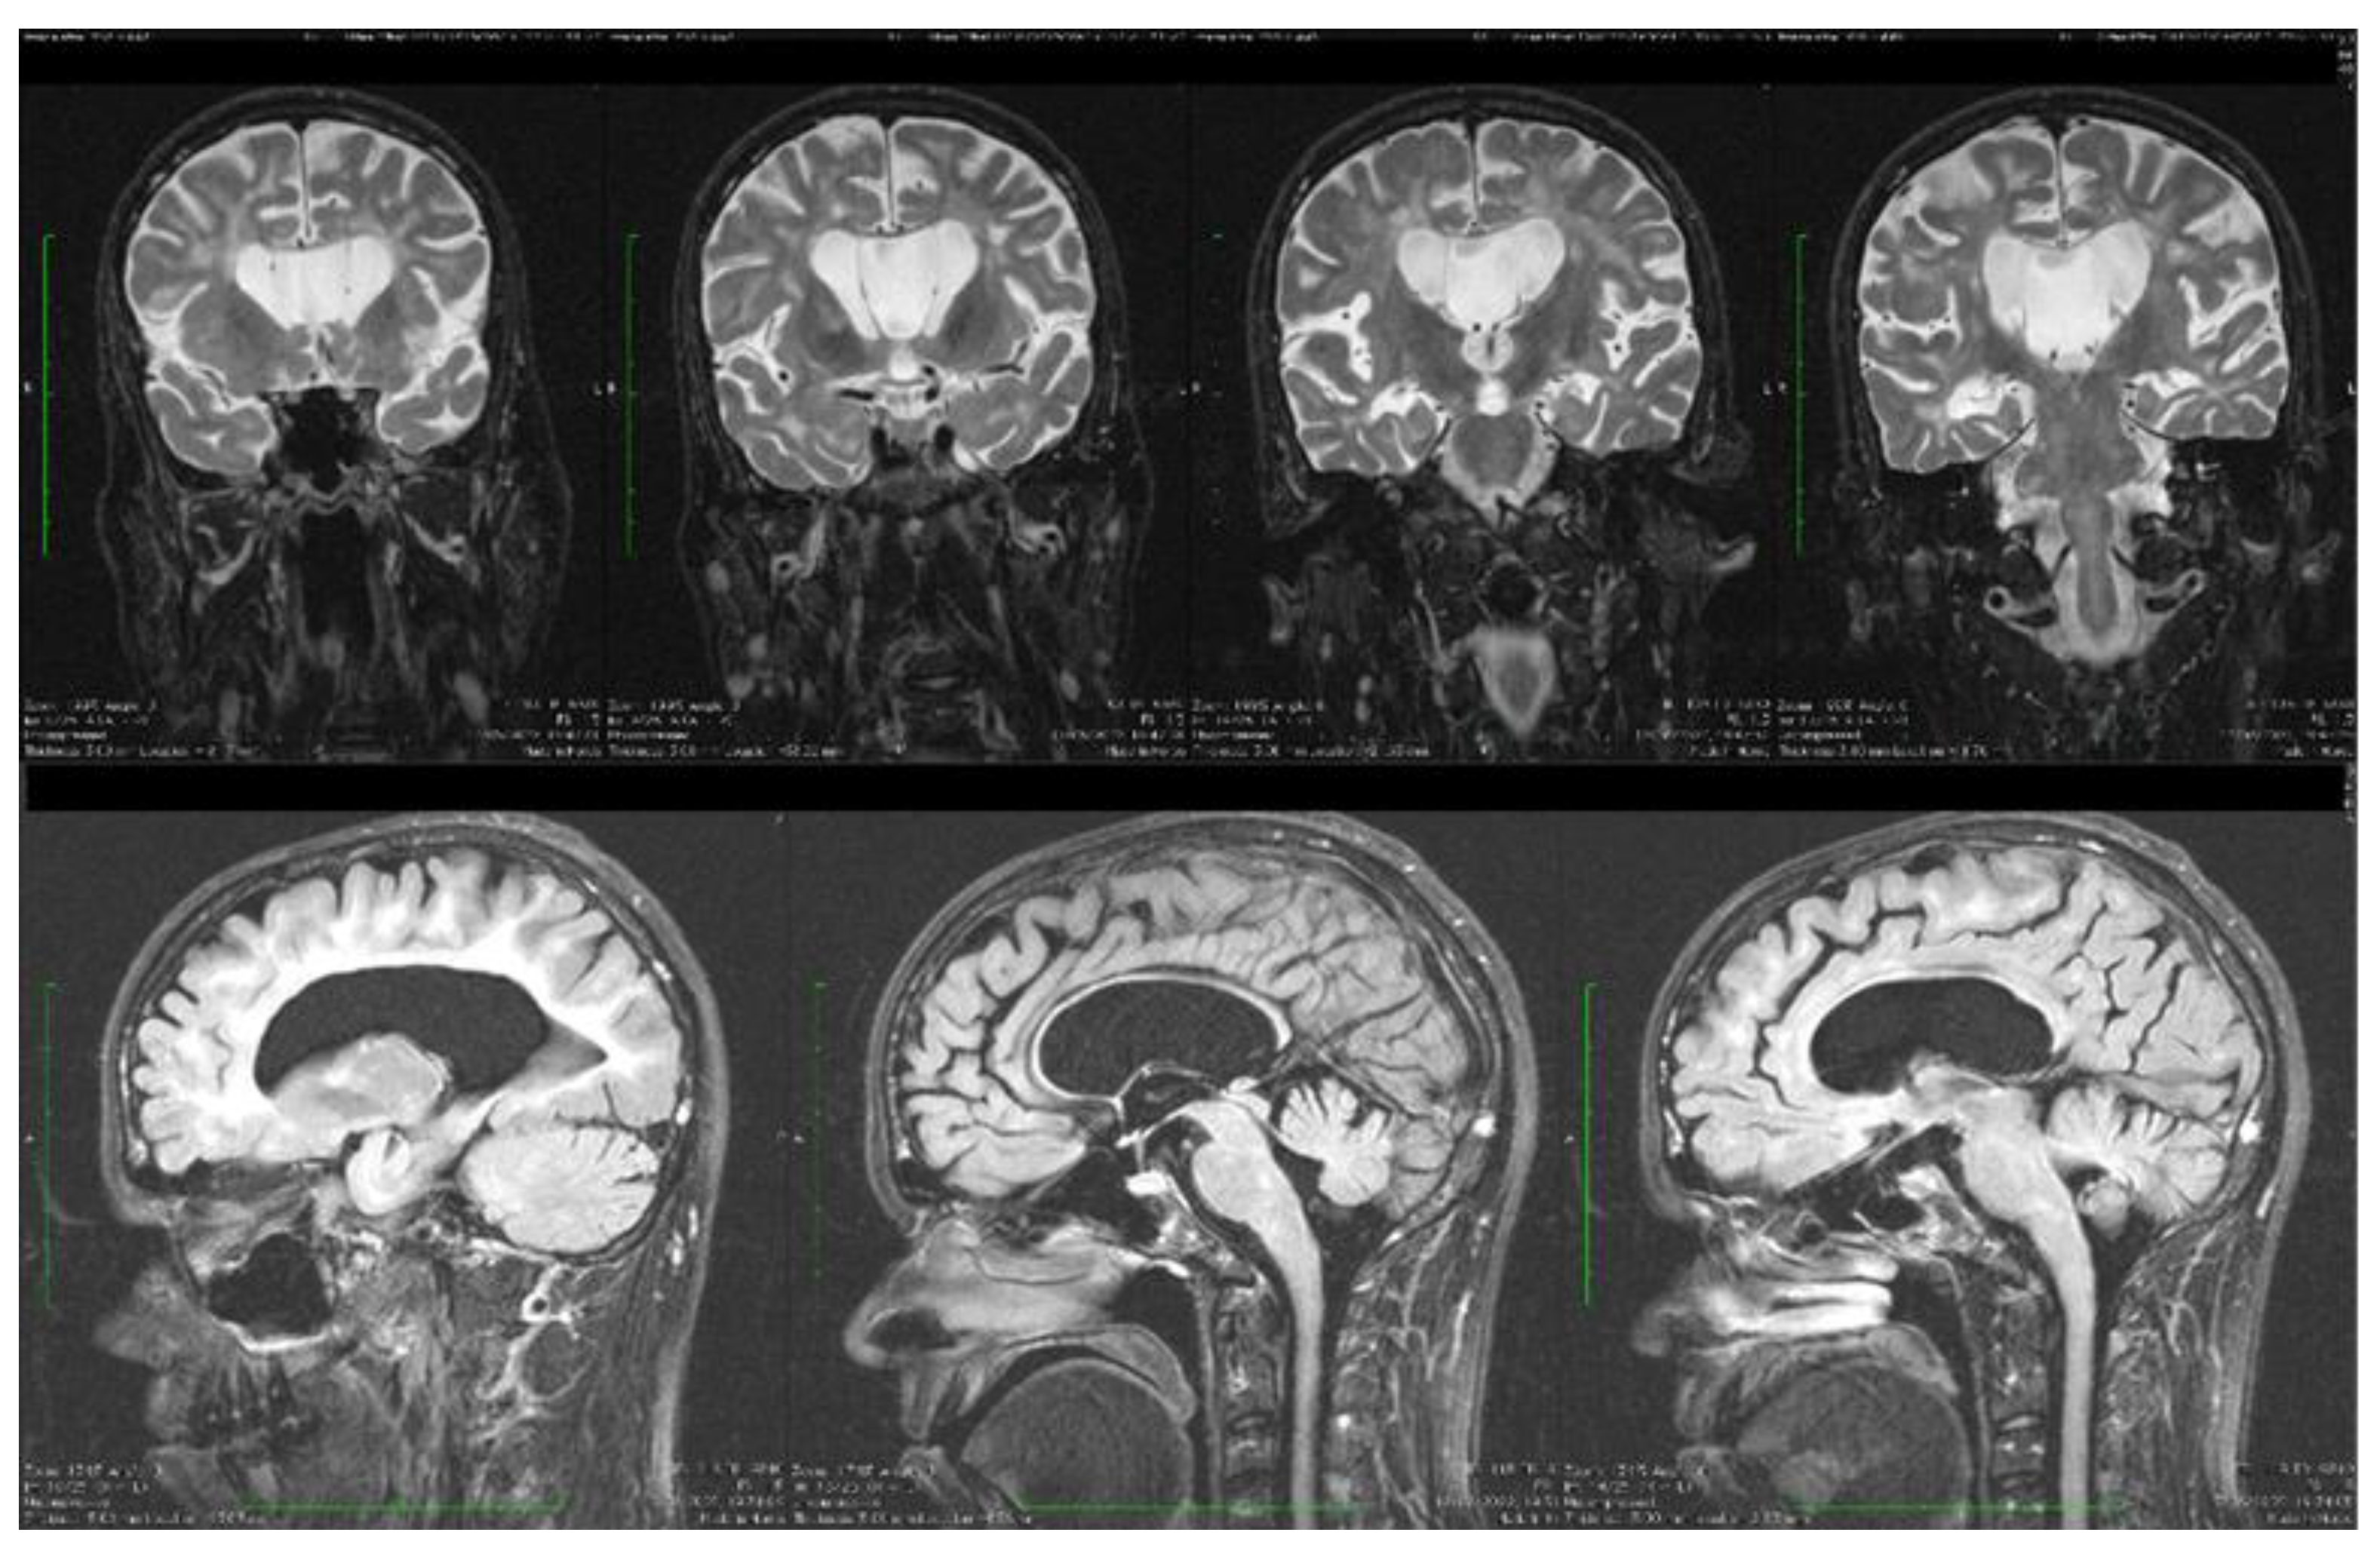

Dynamic evaluations using radiological examination were requested by various neurologists when the patient was 18 and 28 years old. The findings revealed a progressive white matter disorder with cerebral atrophy and progressive enlargement of the CSF spaces. The CT scan performed 13 years and 3 years prior to his admission to our clinic revealed generalized progressive sufferance of white matter with diffuse chronic hypodensities up to 1 cm in diameter (that were more evident at the last brain CT scan examination) at the level of the right internal capsule and lenticular nucleus, cavum septum pellucidi, an enlarged ventricular system, and progressive cerebral atrophy (Figure 2 and Figure 3). The MRI scan performed just before admission revealed severe cerebral atrophy, demyelinating lesions in the pons, middle cerebellar peduncles, supratentorial white matter with chronic lesions in the right and left temporal lobes and the right frontal and parietal lobes, marked atrophy of the right hippocampus in the context of general cerebral atrophy, cavum septum pellucidi, and severe enlargement of the CSF spaces. However, no radiological signs of active hydrocephalus were noted (Figure 4 and Figure 5).

Figure 5. Coronal and sagittal T2 and FLAIR MRI sequences showing wide cavum septum pellucidum, enlargement of the lateral ventricles, diffuse cerebral and cerebellar atrophy, and periventricular white matter hyperintensities.